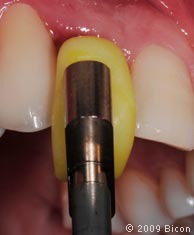

60. Правильное позиционирование коронки по длинной оси штифта абатмента и ложа имплантата происходит с помощью желтого посадочного шаблона из термопластмассы, изготовленного заранее. Шаблон закрепляют на прямом держателе.

61. Правильное позиционирование коронки по длинной оси штифта абатмента и ложа имплантата происходит с помощью желтого посадочного шаблона из термопластмассы, изготовленного заранее. Шаблон закрепляют на прямом держателе.